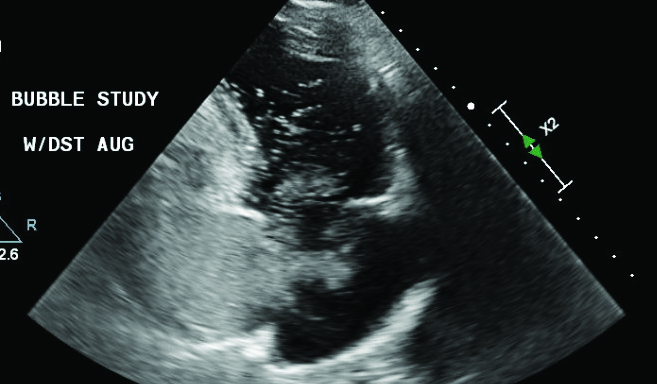

In December 2019, a previously healthy, 39-year-old male immigrant from Honduras was referred for pulmonary balloon valvuloplasty due to significant dyspnea on exertion. Upon initial questioning, the patient disclosed that he had been told as a child in Honduras that he had a “heart problem” and a murmur and was told by those doctors that they could not treat it. His initial labs at presentation to our emergency department showed a hematocrit of 64.6%, and this value increased to >70% in the next 2 days (adjusted normal range at our hospital UCHealth Memorial Central Hospital in Colorado Springs, CO, is 39.2–53.0%). Transthoracic echocardiogram (TTE) at another facility revealed severe pulmonic stenosis, right atrial enlargement, trace tricuspid valve regurgitation, and right ventricular hypertrophy. Cardiac catheterization confirmed these findings and measured a peak gradient across the pulmonic valve of 89 mmHg. The stenosis was successfully treated with a balloon valvuloplasty (Figure 1). The post-procedure pulmonic valve pressure peak gradient was 14 mmHg with no change in tricuspid valve function; a bedside TTE showed trace tricuspid regurgitation (Figure 2).

Figure 1

Figure 1. Fluoroscopy image taken during balloon valvuloplasty of pulmonic valve with a 25 × 4 mm balloon fully inflated and resolution of pulmonary valve indentation.